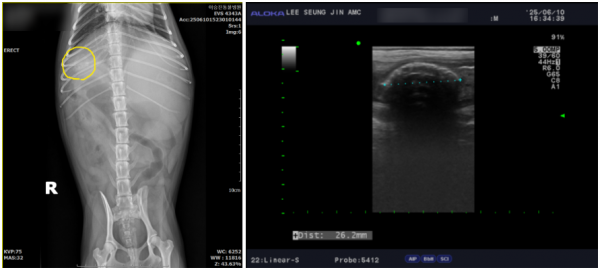

그 결과, 하늘이의 오름십이지장 속 에 씨앗 형태의 이물이 확인되었으며

이로 인해 심한 장염, 복막염, 췌장염이 동반되어 있었습니다.

즉시 내원하여 영상검사(엑스레이·초음파)종합적인 검사를 통해